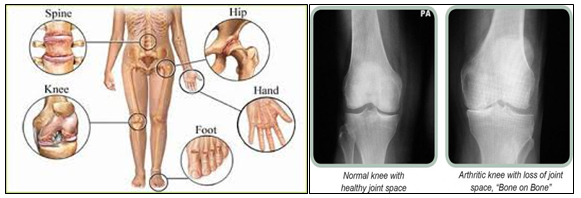

Osteoarthritis is the most common type of arthritis which is due to the progressive degenerative changes in the cartilages and bones participating in a joint. This is more common in old age. The most common symptoms are pain and stiffness. Joint swelling and reduction in range of movements are also seen in certain cases.

This condition starts as mild pain and stiffness,slowly worsening over a period of time, ultimately ending up in complete wearing out of the cartilage and the bony surface. This results in reduction in different movements of the joint. The most common joints affected with osteo arthritis are fingers, shoulder,hip, low back, knee and neck. Excess mechanical stress and strain in the joints due to excess weight, wrong movements and previous injury are the basic reasons for this condition.